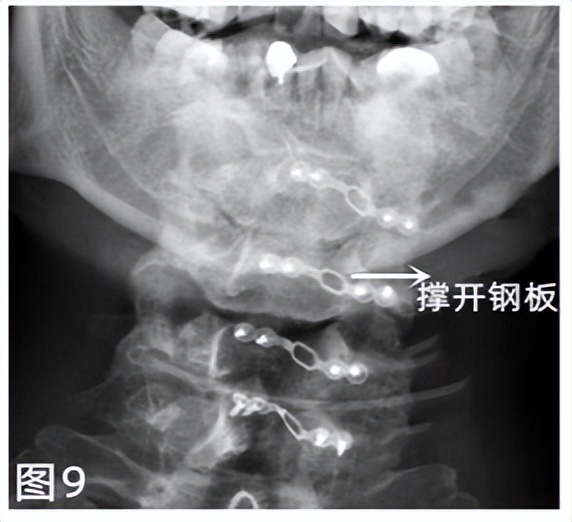

后路手术系自颈后正中切口,将两侧附着的肌肉软组织剥离,显露至颈椎后方结构,将椎板打开(可通过钢板撑开维持),其内容纳的脊髓得到释放,从而起到减压效果(见图 9)。 由于前路手术创伤小,组织破坏少,术后并发症少,如情况允许为首选术式。